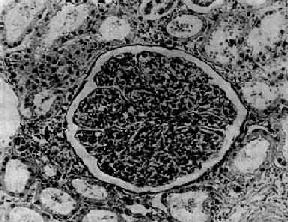

图12-8 毛细血管内增生性肾小球肾炎

电镜下见肾小球毛细血管基底膜表面上皮细胞下有多数驼峰状电子致密沉积物